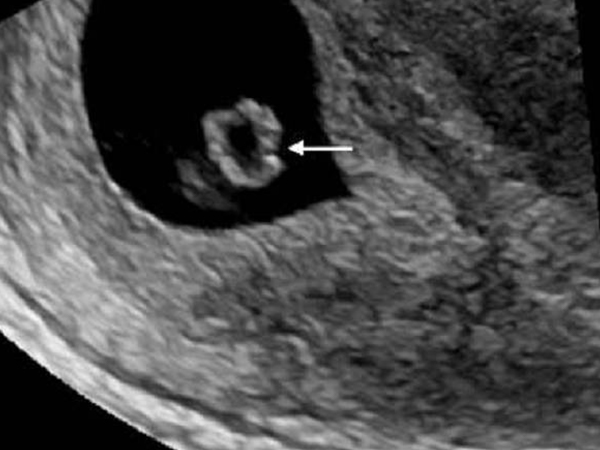

卵黄囊是位于孕囊内部的胚胎组织形式,会随着胚胎的发育逐渐出现,然后又随着胚胎的发育逐渐变小,直至被吸收消失。而卵黄囊出现的时间一般是在4周左右,但是做B超被发现的时间一般是5周以后,而如果在孕八周时做B超还没有发现卵黄囊,那就说明胎儿发育异常可能是受孕失败,需要终止妊娠。

卵黄囊是早期孕囊的标志,是孕囊内部的重要组织形式,没有卵黄囊的孕囊就是一个空壳,无法正常发育成胎儿,因此卵黄囊也是用于判断孕囊是否正常的一个标准。而卵黄囊出现的时间一般是4~12周,但是通常在孕4周是检查不出来的,一般是5~8周才会被发现。

卵黄囊的出现时间是4周以后,根据卵黄囊大小是怀孕时间对照表可知,这时候的卵黄囊刚刚出现,体积较小,但是后期会随着胎儿的发育逐渐增大,而卵黄囊被发现的时间通常是5~8周的时候。

而之所以卵黄囊4周出现,但要5周才能检查出的原因是因为卵黄囊位于孕囊内部,是孕囊的内部的胚胎组织形式,要发现卵黄囊,就需要先发现孕囊,而孕囊可以被B超探查到的时间一般是孕4周以后,因此发现卵黄囊的时间一般是在孕5周以后。